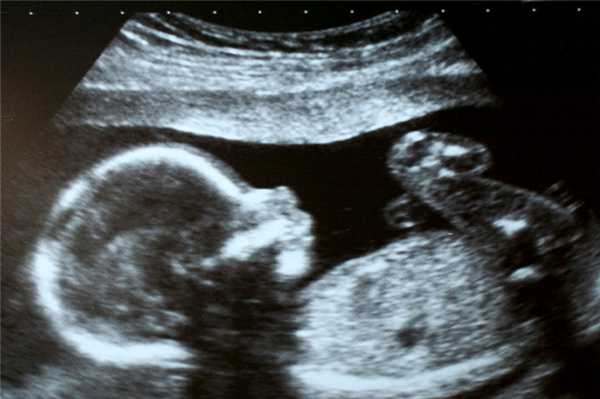

Фото УЗИ ребенка на 21-22 неделе беременности

Визуально во время ультразвуковой диагностики заметно увеличение размеров плода. Его длина на этом сроке достигает 190 мм. Также можно отметить более координированные движения конечностями, возможность поворачивать голову в разные стороны. Также несколько увеличивается слой жировой клетчатки. В остальном плод не сильно отличается от того, что видел врач на 20 неделе во время скрининга.

Фото УЗИ ребенка на 23-24 неделе беременности

В этот период малыш очень активный. Его мышцы и костные структуры позволяют совершать координированные интенсивные движения, а относительно небольшие размеры обеспечивают свободное пространство. Конечности и пальцы удлиняются. Ребенок совершает дыхательные движения, глотая околоплодную жидкость. Его кожа и подкожная жировая прослойка утолщаются. УЗИ на этом сроке назначают редко.

Фото УЗИ ребенка на 25-26 неделе беременности

Основные изменения на этом сроке связаны с активным набором веса и увеличением размеров плода. Скорость сердцебиения составляет 130-160 ударов в минуту. Развиваются функции высшей нервной деятельности, например память.

По снимку УЗИ специалист может оценить динамику развития малыша и заподозрить тяжелые внутриутробные патологии. В этот период ребенок прекрасно виден на фото УЗИ. Такие снимки чаще всего сохраняют для семейного архива.

Фото УЗИ ребенка на 27-28 неделе беременности

На финальной стадии находится развитие всех частей организма малыша. В случае преждевременных родов он уже готов к самостоятельному выживанию. Малыш может открывать глаза, ощущает вкус, слышит все звуки, способен различать запахи. Половые органы полностью сформированы, что позволяет по фото УЗИ точно удостовериться, кого ожидает женщина.